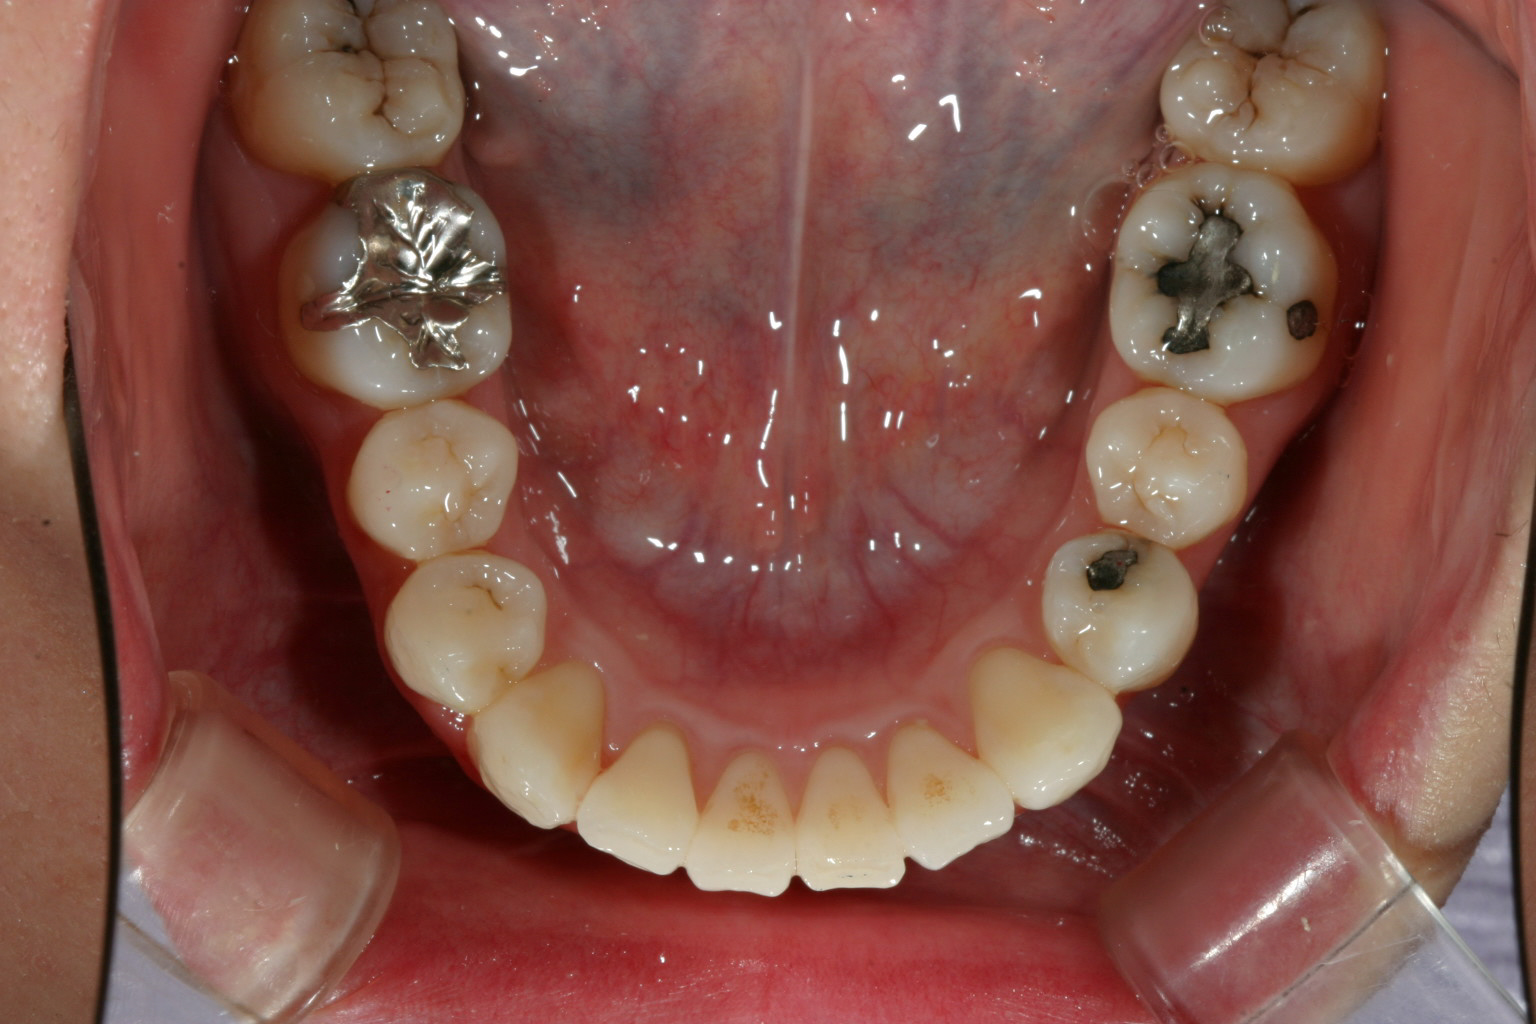

下顎前歯は犬歯間幅径が狭い為ヘビーなガタガタです。

下顎のガタガタも綺麗に改善しました。